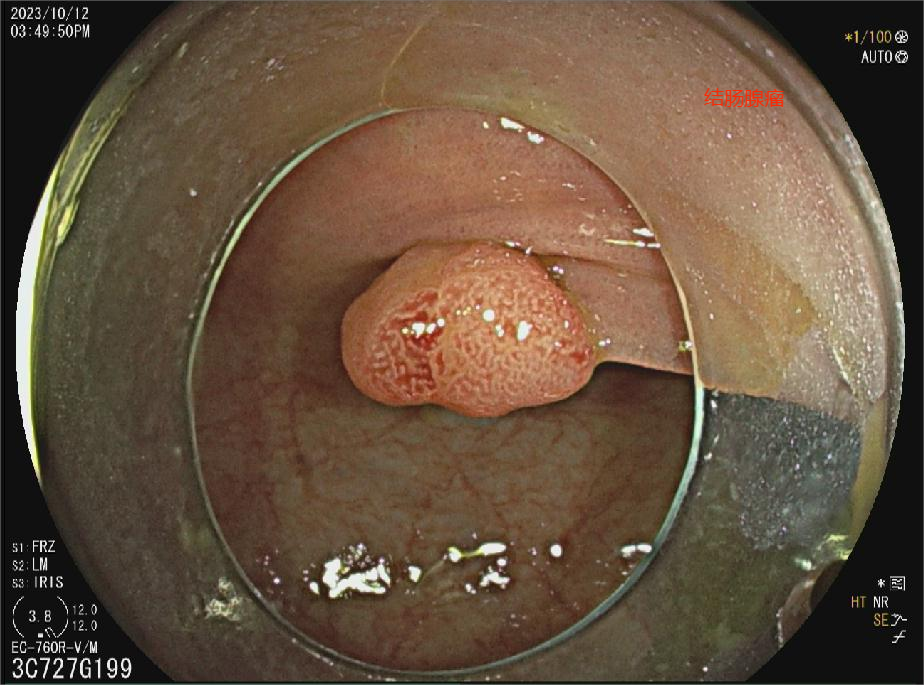

结肠良性肿瘤

结肠腺瘤